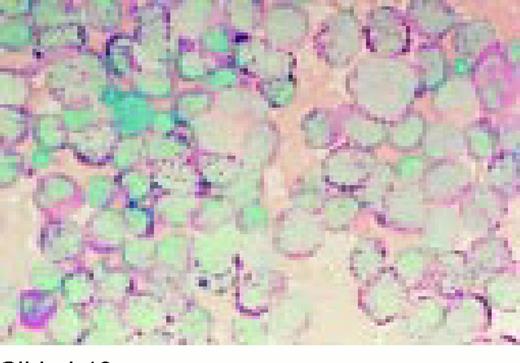

Slide L39

Multiple myeloma, bone marrow aspirate. Virtually every cell in the field is a neoplastic plasma cell. They show nuclear eccentricity, pleomorphism, and a tendency to stick together in clumps.FIG39